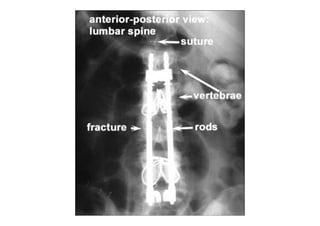

RADIOLOGIA DO

TRAUMA DO ESQUELETO

Referência: http://www.accessexcellence.org/RC/VL/